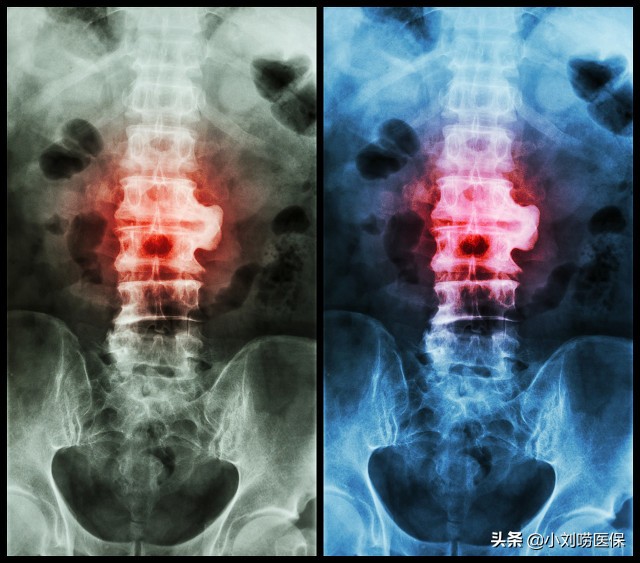

强直性脊柱炎是一种好发于年轻人的慢性病,以15-31岁的人最常见,8岁以下,40岁以上的人几乎没有。大明星周杰伦就有这种症状,这种是一种需长期用药的慢性病,普通门诊是没有医保报销的,慢性病可以申请医保报销,强直性脊柱炎也是一种用药较贵的门诊慢性病,很多地方都把这个纳入了门诊慢性病病种里面,是医保报销的范围。强直性脊柱炎稳定期门诊复查按时按量用药即可,而且用药单纯,纳入医保报销可以减轻患者负担,以前的时候这种病纳入慢性病的地方较少,最近几年各地纳入的就多了。